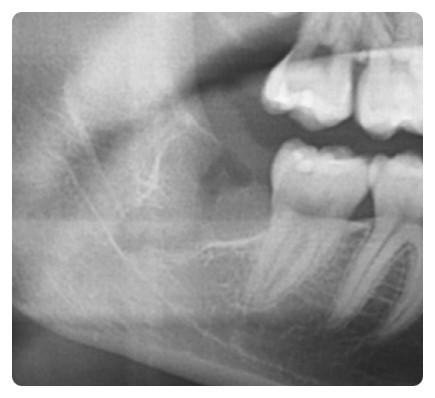

사랑니와 신경관이 붙어 있어 상당히 어려운 케이스입니다.

사진에서 보시는 것처럼 신경관과 사랑니 뿌리가

아주 가까이 붙어 있는 경우에는 상당히 조심을 해야 합니다.

오른쪽은 왼쪽에 비해서 비교적 쉬운 경우이지만

그렇도 이런 사랑니 발치는 상당히 어려운 난이도입니다.

사랑니 뽑기 전 엑스레이 사진입니다.